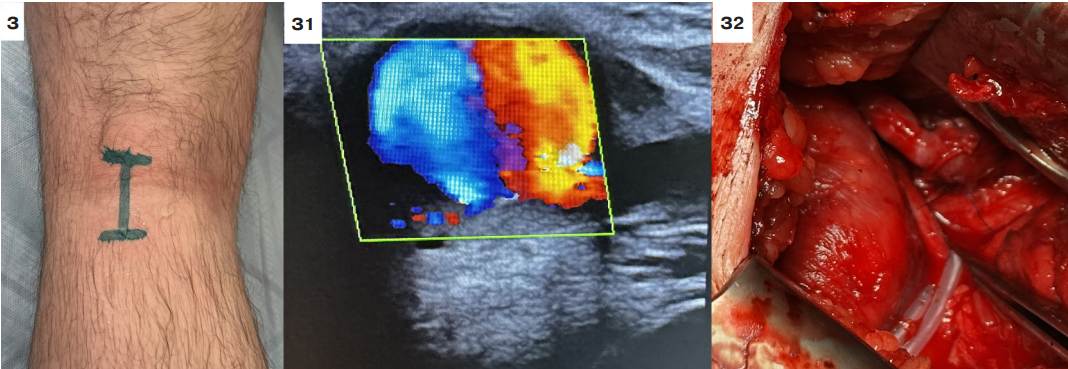

Оперативное лечение псевдоаневризмы подколенной артерии

В указанную когорту больных вошло два случая. У первого из них псевдоаневризма локализовалась на уровне щели коленного сустава. При таких особенностях ее выделение и удаление технически невозможно. Пациенту выполнено бедренно-подколенное аутовенозное протезирование реверсированной БПВ ниже щели коленного сустава из доступов по медиальной поверхности бедра и голени. При этом участок подколенной артерии, содержащий аневризму, перевязан и выключен из кровотока (рис. 3).

Рис. 3. Оперативное лечение псевдоаневризмы подколенной артерии — аутовенозное бедренно-подколенное протезирование.

Примечание: З — проекция псевдоаневризмы подколенной артерии на задней поверхности коленного сустава; З1 — УЗИ снимок псевдоаневризмы подколенной артерии; З2 — дистальный анастомоз между аутовеной и подколенной артерией ниже щели коленного сустава.